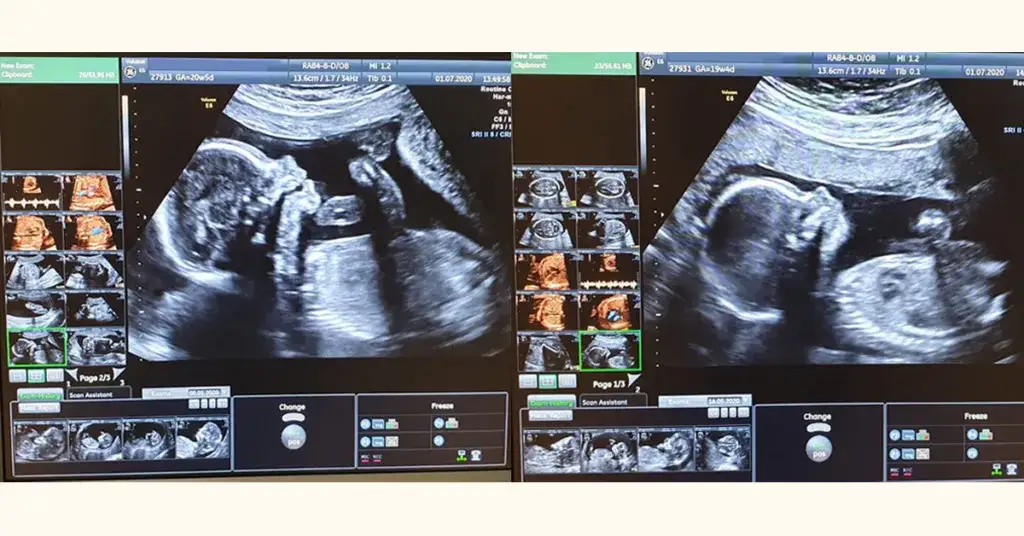

Badania nieinwazyjne są pierwszym krokiem, jaki podejmują przyszłe mamy. Obejmują one różnorodne metody, z których najczęściej wykonuje się ultrasonografię. To badanie pozwala na ocenę anatomii płodu i może wykryć ewentualne nieprawidłowości.

W drugiej połowie ciąży, między 18. a 23. tygodniem, przeprowadza się bardziej szczegółowe badania. To czas na drugie USG, zwane połówkowym, które umożliwia dokładną ocenę wszystkich narządów płodu. W trzecim trymestrze, po 24. tygodniu, kontynuowane są badania mające na celu wykrywanie rzadziej występujących wad serca i innych nieprawidłowości.

Przebieg badań prenatalnych jest różny w zależności od rodzaju wykonanego badania. W przypadku badań nieinwazyjnych, takich jak ultrasonografia, pacjentka jest zapraszana na badanie, podczas którego lekarz używa specjalnego urządzenia do oceny stanu płodu. Cały proces zazwyczaj trwa około 30 minut i jest bezbolesny.